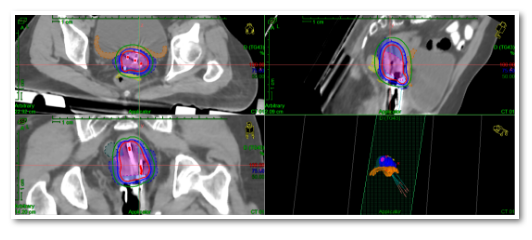

天津医科大学肿瘤医院放射治疗科在院领导和科室主任推动下,积极开展影像引导下的肿瘤个体化三维插植近距离放疗。3月12日,中国抗癌协会近距离放疗专委会常委、天津市医学会妇科肿瘤学分会常委、天津医科大学肿瘤医院放射治疗科副主任医师陈杰团队在近距离治疗室、物理室、CT定位室的密切配合下,针对两名宫颈癌外照射后宫旁肿瘤消退不明显的患者,进行了CT引导下的三维插植后装放疗,成功完成了天津市首例难治性宫颈癌CT引导下三维立体插植近距离放疗

在完成前期准备后,陈杰主任团队将插植针置入患者宫腔,通过放疗专用CT、MR扫描确认并调整插植针的位置,利用三维后装放疗计划系统进行靶区和正常器官的勾画,快速制定放疗计划,精准实施近距离放疗,顺利完成治疗。

精准、规范、个体化治疗是现代放射治疗的发展方向,由影像引导的三维插植后装放疗技术是一种个体化的精准近距离放疗技术,具有局部肿瘤剂量高,危及器官辐射剂量可控的优点,目前在宫颈癌、阴道癌、外阴癌、子宫内膜癌等妇科恶性肿瘤放疗中,展示出了明显优势。

在常规采用的二维腔内后装放疗技术中,放疗靶区剂量不足可能是宫颈癌复发的重要原因之一。而组织间三维插植近距离放疗技术,是结合现代CT、MR等定位引导影像系统,将作为施源器的插植针直接插入肿瘤中心进行放射治疗,打破了解剖结构的限制,与既往二维腔内后装放疗相比具有明显的优势。

影像引导下的三维插植近距离治疗,可以通过三维视角来进行施源器的置入与固定,定位更精确。根据不同靶区,可以采用徒手插植、模板插植、徒手结合模板插植等个体化植入施源器,可以准确地定位肿瘤组织的位置,通过非共面多角度进针,使肿瘤放疗靶体积达到处方剂量要求,在给予高剂量照射的同时,保证肿瘤周围正常组织受到照射的剂量控制在可接受范围内,从而提高患者的治疗效果和安全性,为晚期难治性的妇科肿瘤患者提供了新的治疗希望。